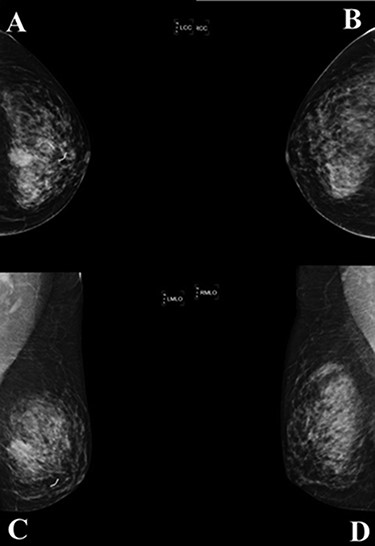

A mammogram of the breasts revealed a mass with angular and ill-defined boarder at palpable area in left mid breast size 23 × 19 mm. (A; left cranial caudal view, C; left mediolateral—oblique view), comparison with the right breast (B; right cranial caudal view, D; right mediolateral—oblique view).

complex. The left axillary lymph node was found to measure 1 cm after palpation. A mammogram revealed an ill-defined mass at sub-areolar on left breast with angulation 2.3 × 1.9 cm, without suspicious microcalcification or architectural distortion (Fig. 1). Core needle biopsy revealed invasive ductal carcinoma (IDC). Immunohistochemical study (IHC) showed Estrogen receptor (ER), Progesterone receptor (PR), and Human epidermal growth factor receptor 2 (HER2) negative. Fine needle aspiration of left axillary lymph node revealed poorly differentiated metastatic lymph nodes. Metastatic workups were unremarkable. Left lumpectomy and axillary lymph nodes dissection were performed. The final pathology reported ACC measuring 3.5 cm in greatest dimension, lymphovascular invasion, presenting with DCIS, comedonecrosis type, high grade nuclei, microcalcification, all margins are negative for malignancy (Fig. 2). IHC showed CD117 and CK7 positive for malignant ductal cell of tumor, CK5/6 and p63 positive for myoepithelial cells within the tumor. ER, PR and HER-2 were negative. Ki-67 was strongly positive 3 + of nuclear staining, 30% of neoplastic cells (Fig. 3). One of 21 lymph nodes demonstrated metastatic ACC with extranodal extension (Fig. 4). Metastatic part is 0.9 cm in greatest dimension. Postoperative adjuvant chemoradiotherapy was given.